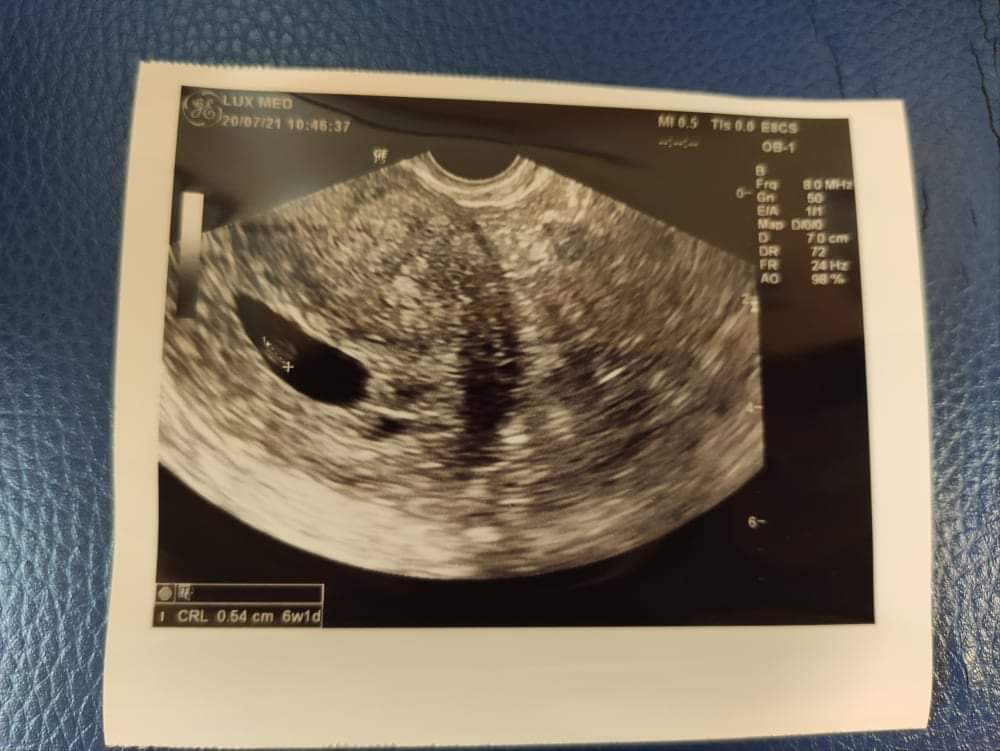

Ja tego samego dnia w odstępie 3 godzin byłam u dwóch ginekologów i miałam dwa USG. U pierwszego wiek był na 6+1 bodajże, a powinno być 7+3. W 5+4 byłam u innego ginekologa i wiek był na 5+4. Niemożliwe, żeby przez tyle dni była taka mała różnica w wieku ciąży. Zarodek 0.54 cm. Ala plamka I nic wiecej. Nawet serca nie sprawdzal. Nastresowalam się jak nie wiem. Na szybko szukałam ginekologa z lepszym sprzętem. U drugiego wiek na 7+3 i zarodek bodajże 1.21 cm. Różnica ogromna. Ponad dwa razy większy. No w kilka godzin tak nie urósł 🤣 Serduszko widziałam na monitorze, a zarodek miał zalążki nóżek, rączek.

Tu masz moje USG z tego samego dnia na dwóch różnych sprzętach. Sama porównaj.